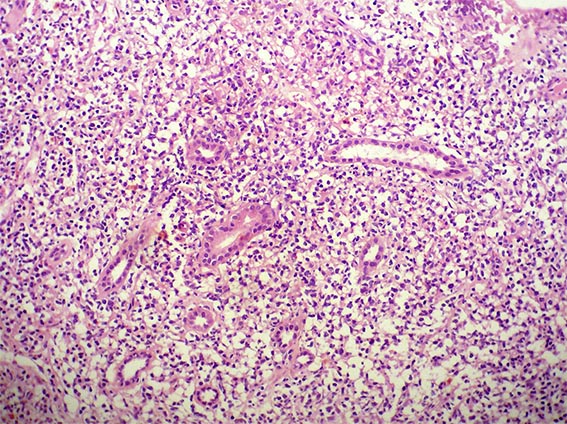

The patient is a 41-year-old woman with constitutional symptoms. Among the many studies undertaken to determine its cause, pyuria and microscopic hematuria were found in the urinary sediment, and, by ultrasonography, a ill-defined mass was evidenced on the renal upper pole of the left kidney.

A biopsy of the mass was obtained. See the images.

Figure 1. H&E, X200.